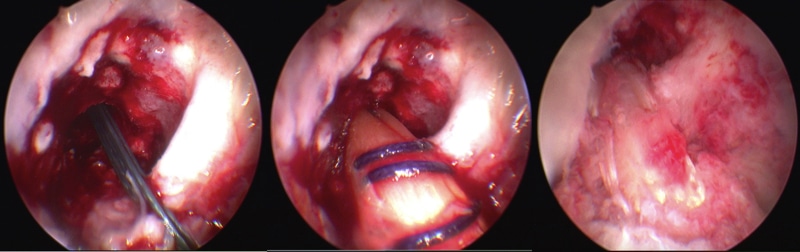

- Surgical reconstruction of the ACL (Fig. 4) involves the use of a tendon or an artificial graft

- This is not performed acutely but following a period of ‘prehabilitation’, whereby the patient will engage with a physiotherapist for a period of months prior to the surgery

Figure 4 – An arthroscopic reconstruction of right ACL ligament using an autograft

- Acute surgical repair of the ACL is possible in some cases dependent on the location of the tear within the ligament

- If the imaging on MRI is favourable, the patient can be further assessed under GA knee arthroscopy, proceeding to an acute repair where possible, which involves re-suturing the ends of the torn ligament together